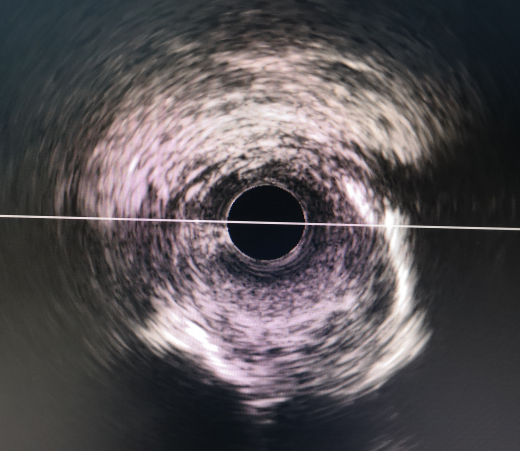

支架植入前 支架植入后

IVUS指导下可以给术者提供更准确的数值参考来进行支架植入,并对支架植入后支架的膨胀程度贴壁情况等都可以有很好的评估作用